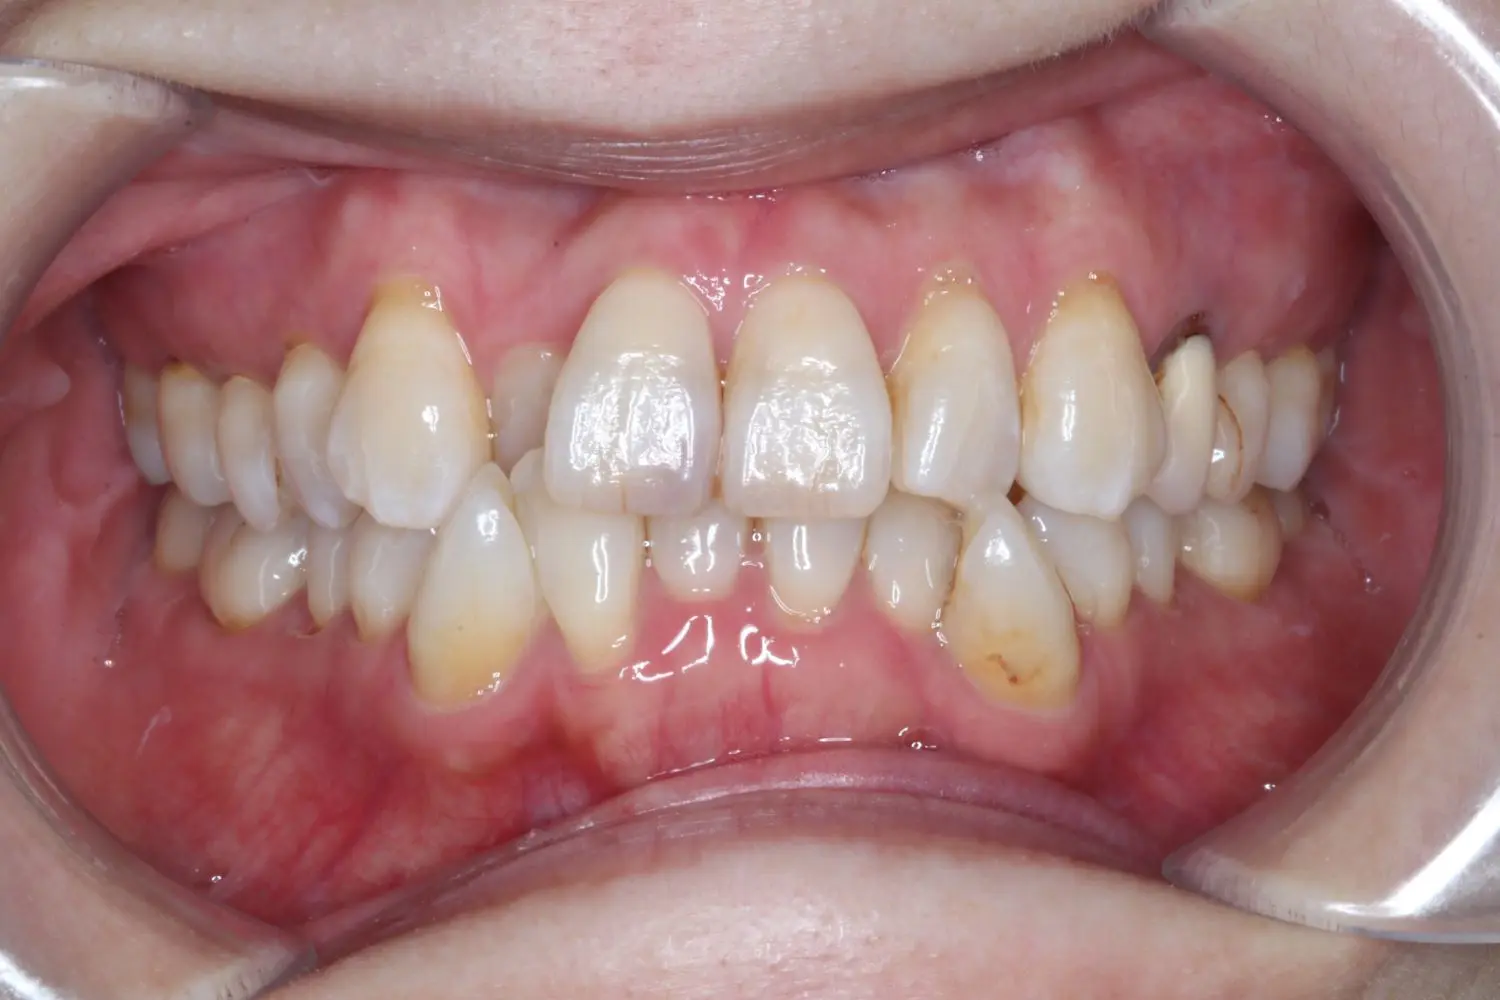

| 年齢 | 50代女性 |

| 主訴 | ガタガタ |

| 治療期間・治療回数 | 2年3か月 |

ガタガタの程度が強いため、4本抜歯することで叢生を改善するスペースを確保しました。年齢とともに歯が動きづらくなりますが、矯正治療は十分に行えます。無理のない治療計画で歯肉退縮など副作用を抑えられました。